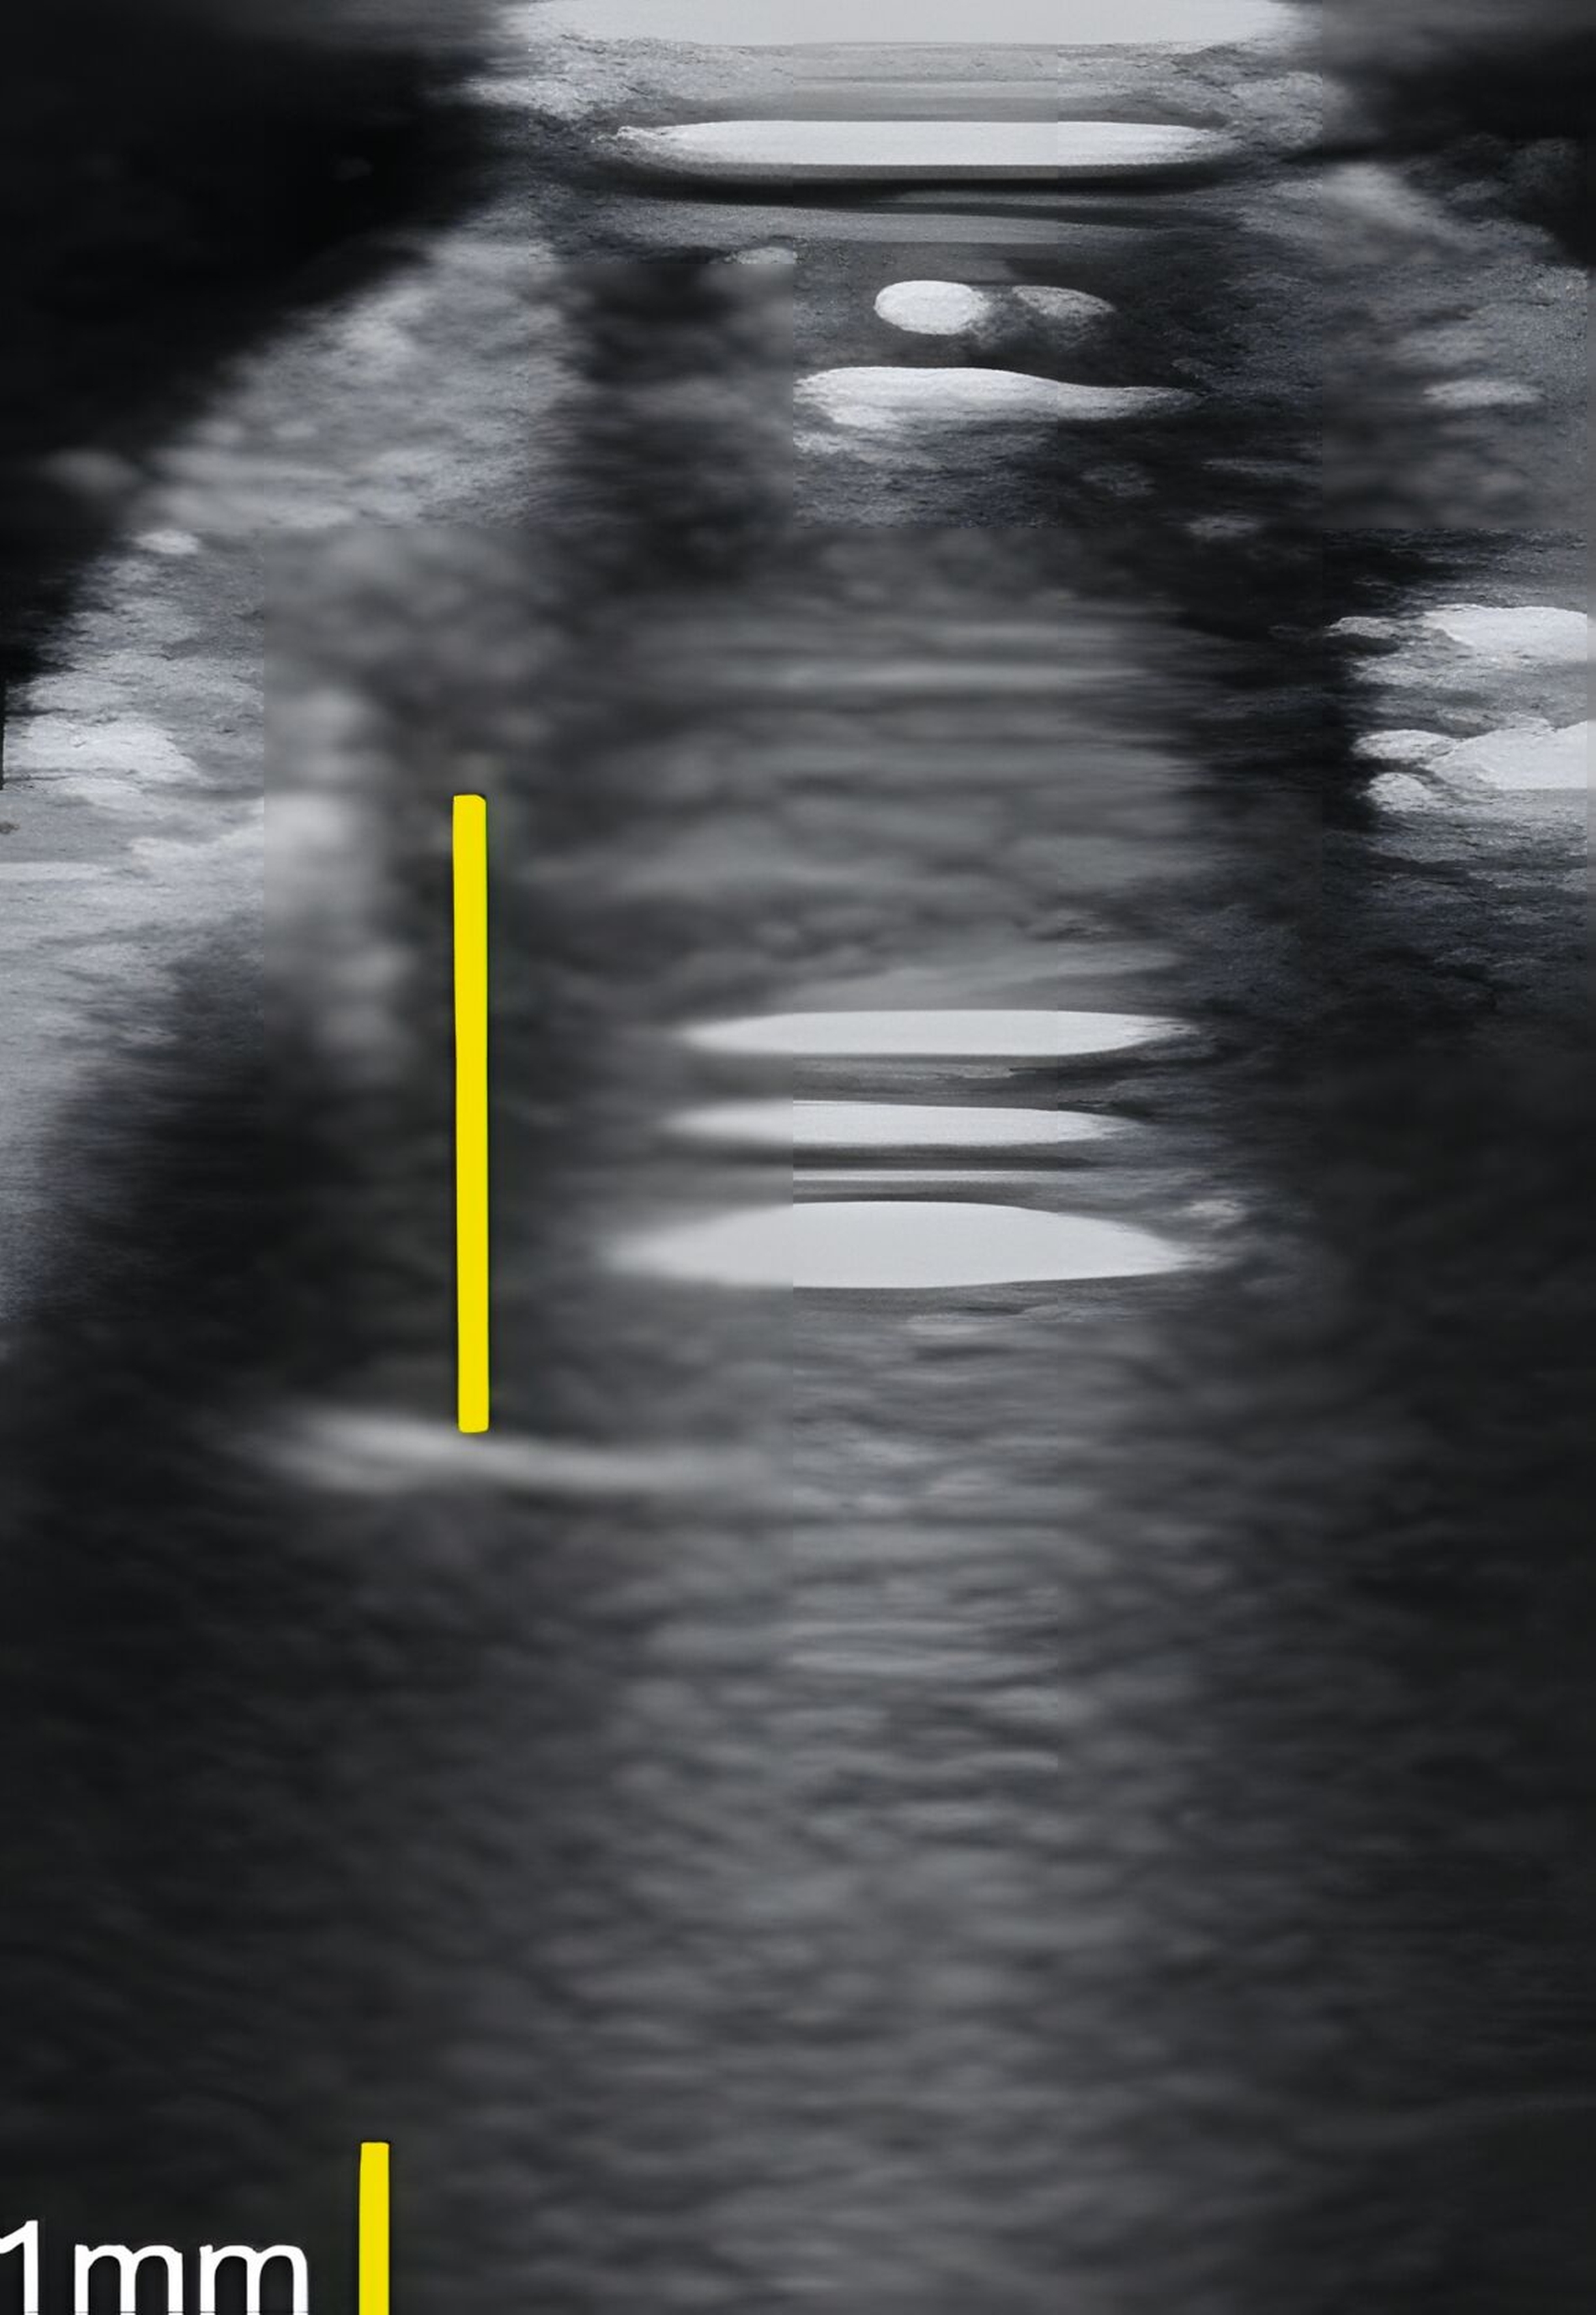

Dies konnte in einer ebenfalls eigenen humanen Kadaverstudie bestätigt werden [Bykhovsky et al., 2024]. Dabei wurden an Implantaten standardisiert Fenestrationen (n = 7), Dehiszenzen (n = 14) und dreiwandige Knochendefekte (n = 6) präpariert (Abbildungen 6 bis 8). Die Defekte wurden mit US- und DVT-Aufnahmen untersucht und die Messungen mit den direkten Messungen verglichen. Die US-Messungen zeigten eine starke Korrelation mit den direkten und den DVT-Messungen. Die sonografische Messgenauigkeit war bei Dehiszenzen am höchsten, gefolgt von Fenestrationen und dreiwandigen Knochendefekten.